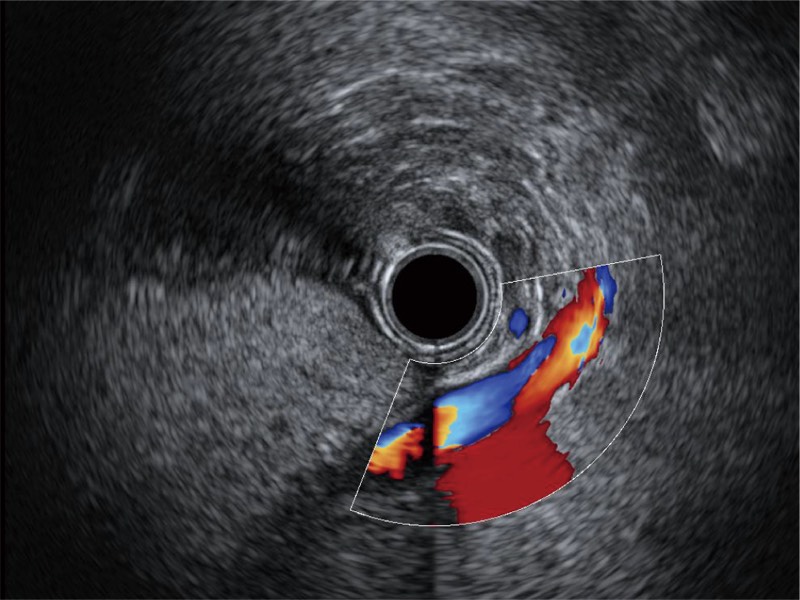

清晰显示胆总管及周围血管分布